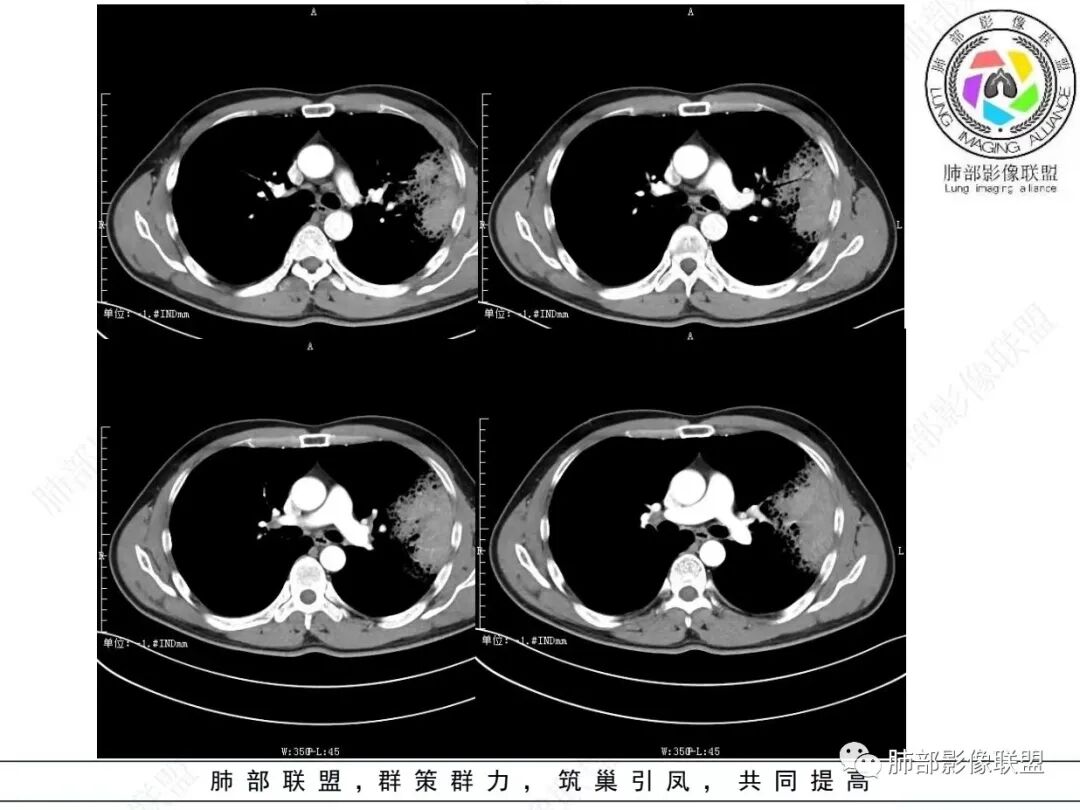

左肺上叶大片状实变影混合磨玻璃影,其内可见蜂窝征,增强扫描明显强化,进入病灶血管边缘有侵犯,结合病史,考虑肺炎型肺癌。鉴别诊断大叶性肺炎。

中年男性,咳嗽咳血,影像表现左肺上叶片状阴影,周围可见多发磨玻璃影,病灶内支气管僵硬,增强病灶内可见血管造影征,病灶与胸膜可见栽赃,考虑恶性病变,粘液性腺癌。

左肺上叶胸膜下实变伴周围边缘磨玻璃,其内可见枯枝征及蜂窝,不均匀强化,可见低密度影,血管显示尚可,考虑肺炎型肺腺癌

左肺上叶胸膜下大片状实变区,周围散在磨玻璃影,局部膨隆,界清,近端气管截断,叶间胸膜局部稍膨隆,增强扫描实变区轻度强化,内走形血管僵硬,轮廓毛糙,胸膜栽赃,半年病史考虑恶性,粘液性腺癌

左肺上叶大片状实变密度影,边缘见磨玻璃密度,呈外向内生长,内可见多发支气管影,走行僵直,增强后实变部分明显不均匀强化,血管纤细,考虑粘液腺癌可能大

男,46,咳嗽半年,加重10天,白粘痰,偶有痰血。胸部CT:左肺上叶舌叶大片实变影,边缘GGO,长轴沿胸膜及叶裂展开,重力依赖,胸膜叶裂阻隔,内见蜂窝,钱币征,枯枝。强化不均匀,血管造影征。考虑粘液腺癌,鉴别大叶性肺炎、干酪性肺炎等。

实变区内有低密度带,强化偏低,欠均匀

支气管近端通畅,实变区远端堵塞,腔内有粘液栓

血管走形尚自然,没重建血管,没有明显血管受侵

2.左肺上叶大片状混合密度影,未见空洞,实变影主要位于胸膜下,长轴与胸膜平行,实变区内部密度不均、其内可见多发小斑片状低密度影,磨玻璃影多位居肺门一侧,可见网格,磨玻璃影边界多可分辨,重力分布趋势。病灶区支气管显示较为通畅,进入外围实变区渐至消隐。病灶轻度不均匀低强化,病灶区肺动脉显示较良好,未见破坏。